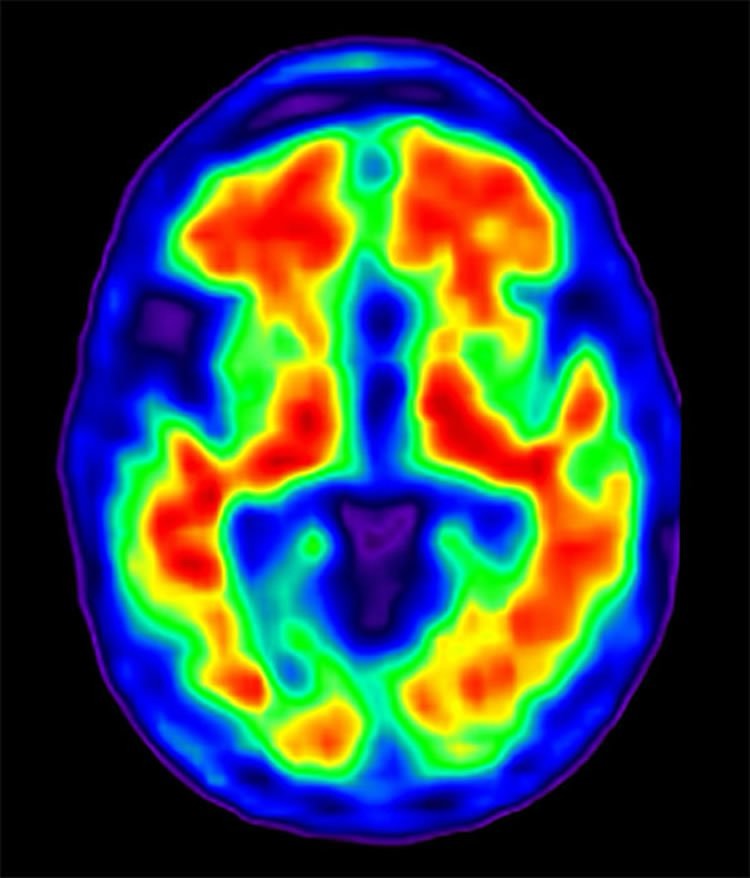

Dementia is a general term for a decline in cognitive function that interferes with daily activities. Alzheimer’s disease is the most common type. While there’s no cure, emerging evidence suggests that lifestyle modifications can significantly reduce your risk. It’s like upgrading your brain’s software to optimize its performance.